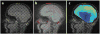

Rapid deformation of brain tissue in response to head impact or acceleration can lead to numerous pathological changes, both immediate and delayed. Modeling and simulation hold promise for illuminating the mechanisms of traumatic brain injury (TBI) and for developing preventive devices and strategies. However, mathematical models have predictive value only if they satisfy two conditions. First, they must capture the biomechanics of the brain as both a material and a structure, including the mechanics of brain tissue and its interactions with the skull. Second, they must be validated by direct comparison with experimental data. Emerging imaging technologies and recent imaging studies provide important data for these purposes. This review describes these techniques and data, with an emphasis on magnetic resonance imaging approaches. In combination, these imaging tools promise to extend our understanding of brain biomechanics and improve our ability to study TBI in silico.